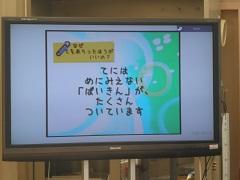

11/29 3年生手洗い指導・後半

早速教わったように手を洗います。水は冷たかったけれど一生懸命に洗いました。

洗った後で、今度はライトの下に手をかざします。

よく落ちている所と、汚れが残った所がありました。

最後にもう一度ビデを見て確認しました。塩谷病院の看護師先生方ありがとうございました。

11/28 3年生手洗い指導・前半

3年生の手洗い指導の様子をお伝えします。1年生に続き今度は3年生です。

講師の先生は、塩谷病院の看護師の方々です。子供たち手に何か付けていますね。

看護師の先生からシュッとされています。これを両手に良くもんでこすります。

そしてライトを当てると汚れが浮かび上がりました。

11/26 1年生手洗い指導・前半

1年生の手洗い指導の様子を2回に分けてお知らせします。

先生は塩谷病院の看護師のみなさん、3人です。最初にビデオを見せてもらいました。

ビデオを見ながら子供たちは手を動かして洗い方をやっています。

うがいのしかた、マスクのつけかたも教えてもらいました。